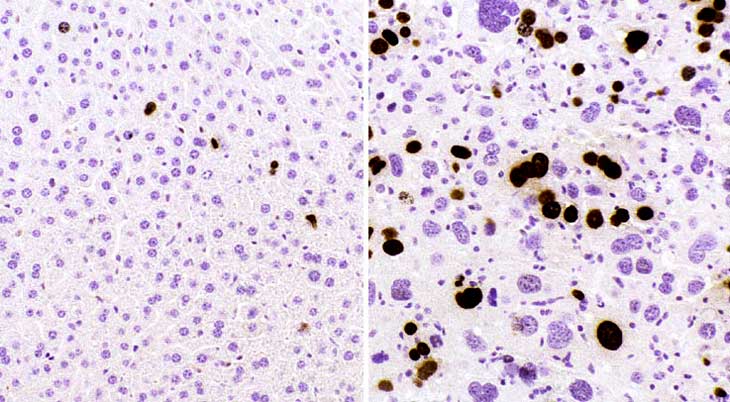

Bromodeoxyuridine immunohistochemistry from a normal liver showing a low labeling index and from a 39-day-old mouse with a high labeling index.